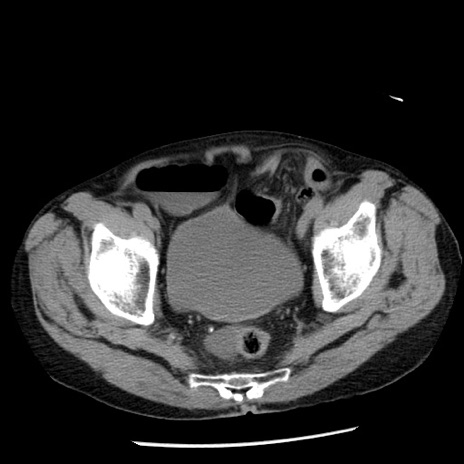

症例26(横断像)

【症例】80歳代男性

【主訴】嘔吐

【現病歴】昨晩2回嘔吐あり、今朝になっても嘔吐あり。来院。

【既往歴】胃潰瘍

【身体所見】意識清明、BT 37.6℃、BP 166/95mmHg、HR 100bpm、SpO2 97%、腹部:平坦・軟、腸蠕動音聴取良好、圧痛なし。

【データ】WBC 21900、CRP 1.46